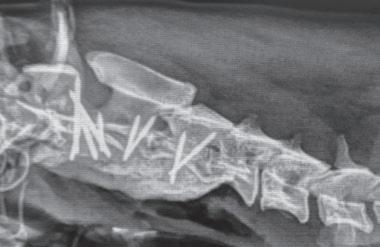

Tratamiento quirúrgico de la subluxación atlantoaxial 30

• Tratamiento quirúrgico de la subluxación atlantoaxial